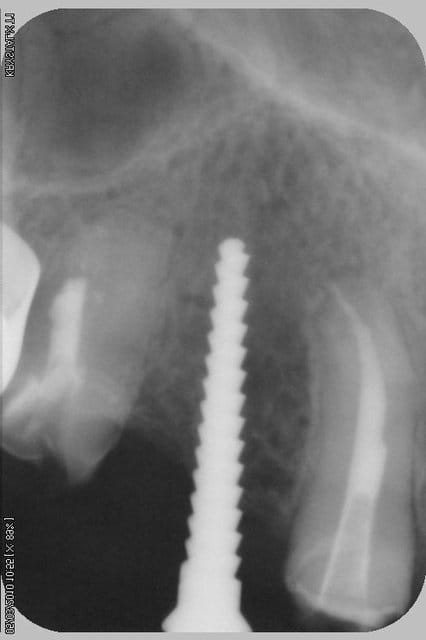

tiens...un ptit cas...

dans ce petit cas...j'ai commencé avec le kit MIS...et fini ma voie crestale avec le kit HBS...

ok, c'est un mini soulevé...mais bon , c'est un exemple...

juste une précision...premier foret 1.3mm sur 8mm...expansion pour mettre un implant de 4x10...

j'ai juste "léché" la préparation du site final avec le foret terminal du système...sur 8mm...avant d'insérer l'implant...stab primaire au top...blocage à 40 Ncm...

rien...une cloison du sinus...;-))

???? tu as un pano ou un scan je ne situe pas ça comme une cloison, mais je vois mal.

j'ai la pano au cab...pas de problème...çà peut aussi être un épaississement de la membrane dans ce cloisonnement...il a eu un bon rhume quelques semaines avant...